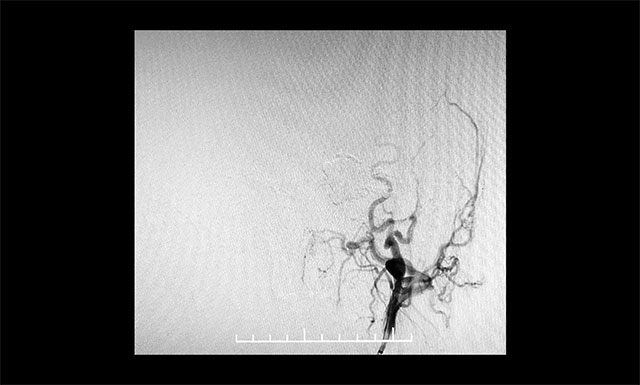

DSA 檢查顯示,左側(cè)天幕區(qū)硬腦膜動靜脈瘺,瘺口血流大,供血來源廣泛,引流靜脈有瘤樣擴(kuò)張。

DSA檢查顯示,左側(cè)天幕區(qū)硬腦膜動靜脈瘺

▲ DSA檢查顯示,左側(cè)天幕區(qū)硬腦膜動靜脈瘺